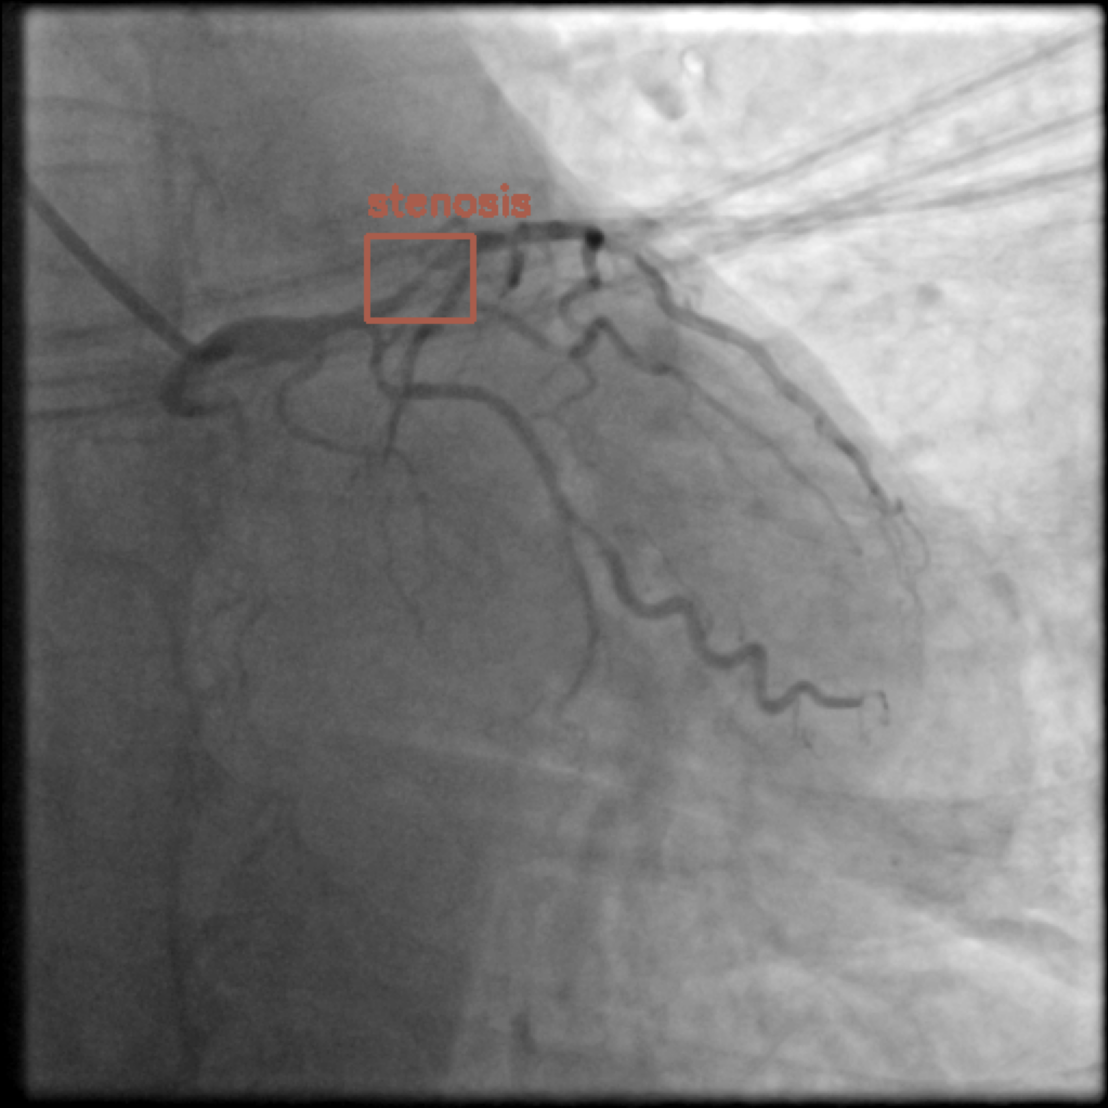

Figure 1 shows sample images from the ARCADE dataset with annotations for stenosis detection. The annotations highlight regions of arterial narrowing, providing ground truth data for training and evaluating object detection models.

To further assess the detection performance, qualitative results for three test images are presented in Figure 2. The first column shows the original images with ground truth annotations. The second, third, and fourth columns depict detections from DINO-DETR, Grounding DINO, and YOLO, respectively.

(a) Original (b) DINO-DETR (c) Grounding DINO (d) YOLO

The qualitative comparison in Figure 2 reinforces the trends observed in the quantitative evaluation. DINO-DETR produced fewer detections, occasionally missing relevant stenotic regions, consistent with its conservative detection strategy aimed at minimizing false positives [6]. Grounding DINO, although capable of identifying more regions, sometimes resulted in cluttered predictions due to over-detections [7]. YOLO provided a reasonable trade-off by effectively capturing anatomical structures while maintaining relatively high confidence scores and clear visualizations [5].